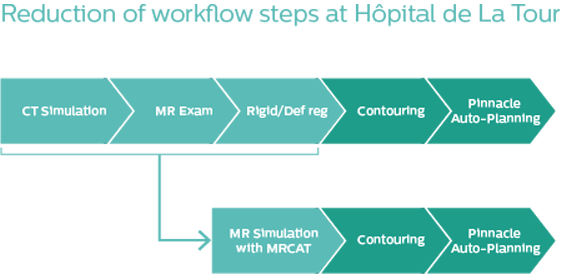

MR-only radiotherapy planning drives a good patient experience

When MR-only radiotherapy planning is performed, no CT simulation of the patient is needed. Even from the start, there was no doubt that Hôpital de La Tour was going to provide MR-only radiotherapy planning for their pelvic cancer patients.

MR-only radiotherapy planning with MRCAT

Simpler workflow, more confident pelvic contouring

The introduction of MR-only simulation for pelvic cancer radiotherapy planning has streamlined the workflow and increased confidence in target and OAR delineation, according to the La Tour team.

The simulation workflow is straightforward, with the RTT performing the positioning using the anterior coil support to prevent contact of the coil with the patient. No external laser positioning system is used. Instead, the La Tour team relies on the internal laser and a house-made ruler system for origin localization. Daily CBCT soft tissue matching against the MRCAT image set is performed, leading to a lean and satisfying workflow.

"We save more than an hour-and-half in plan preparation as compared to a workflow where we would register CT with diagnostic MR series that are not designed to RT needs," Mr. Bolard notes. “We also increase accuracy, since typical diagnostic sequences use large slice thicknesses and limited FOVs, which makes registration difficult to perform.”

“We have benefited not only from more precise tumor delineation and better OAR sparing, but also the elimination of the uncertainties of image fusion is particularly important,” he says. “It is also clearer and simpler for patients, who are now prescribed a single appointment to prepare for their treatment.”

“The logistical benefits are significant,” Dr. Champion adds. “MR-only radiotherapy avoids the need for an additional imaging examination and also reduces the costs associated with treatment planning. It’s also noteworthy that decreasing the number of examinations relieves the booking staff of these.”